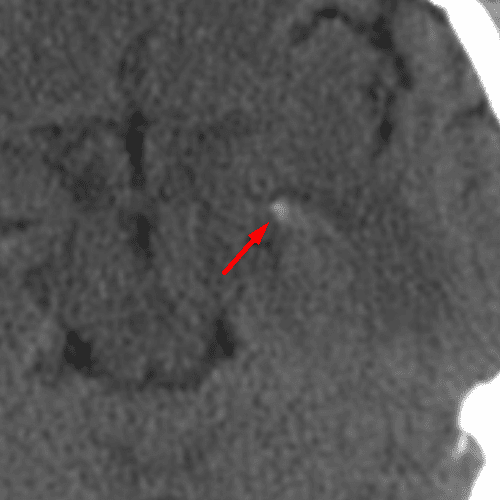

Cortical Vein

Case 10